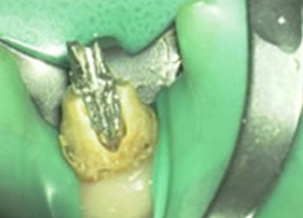

移除鈣化物後找到消失的根管

治療後